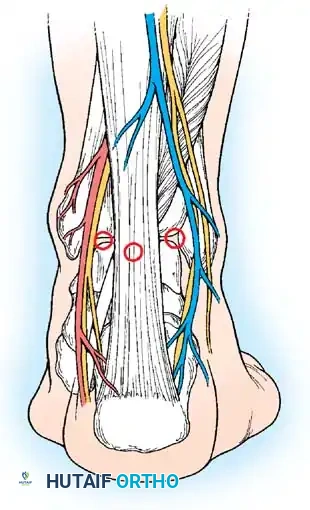

Posterior Portals

Access to the posterior compartment is essential for addressing posterior impingement (os trigonum syndrome), posterior loose bodies, and posterior talar dome lesions.

Posterior portals diagram detailing the relationship to the Achilles tendon, sural nerve, and posterior tibial neurovascular bundle.

Clinical photograph showing the marking of the posterior portals.

1. Posterolateral Portal

* Location: Located immediately lateral to the Achilles tendon at or slightly above the level of the joint line.

* Structure at Risk: The sural nerve and the small saphenous vein.

* Technique: The proper level is determined by arthroscopically viewing the entrance of an 18-gauge spinal needle placed just posterolateral to the tendon. The surgeon must avoid straying too far anteriorly to protect the sural nerve.

2. Posteromedial Portal

* Location: Located at the level of the joint line, just medial to the Achilles tendon.

* Structure at Risk: The posterior tibial artery, tibial nerve, and the medial calcaneal branch of the tibial nerve.

* Safety Profile: Sitler et al. evaluated the safety of posterior portals in the prone position. They found that 54% of the posterior talar dome could be visualized. The average distance to neurovascular structures was 3.2 mm to the sural nerve (laterally) and 6.4 mm to the tibial nerve (medially). Extreme caution is required.

If the posterior compartment cannot be adequately visualized from anteriorly, a posterolateral portal must be established. Insert an 18-gauge needle just lateral to the Achilles tendon, approximately 1 cm distal to the corresponding anterior portal (to account for the curvature of the talar dome), which places it roughly 1.5 to 2 cm above the tip of the lateral malleolus.